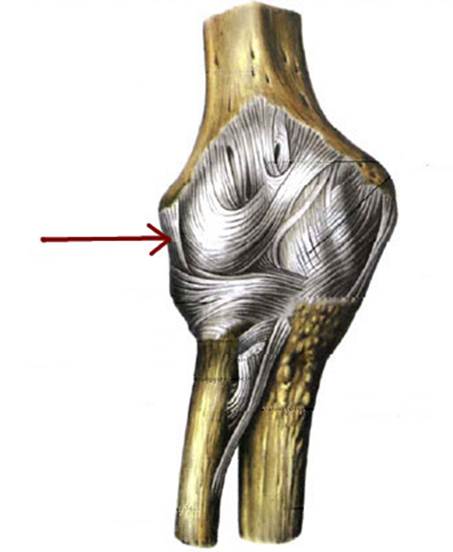

I:

S: Стрелка указывает на lig. Collateralis ulnare

I:

S: Стрелка указывает на lig. Anulare radii

I:

S: Стрелка указывает на lig. Collaterale radiale

S: Стрелка указывает на плече-лучевой сустав (русский язык).

S: Стрелка указывает на плече-локтевой сустав (русский язык).